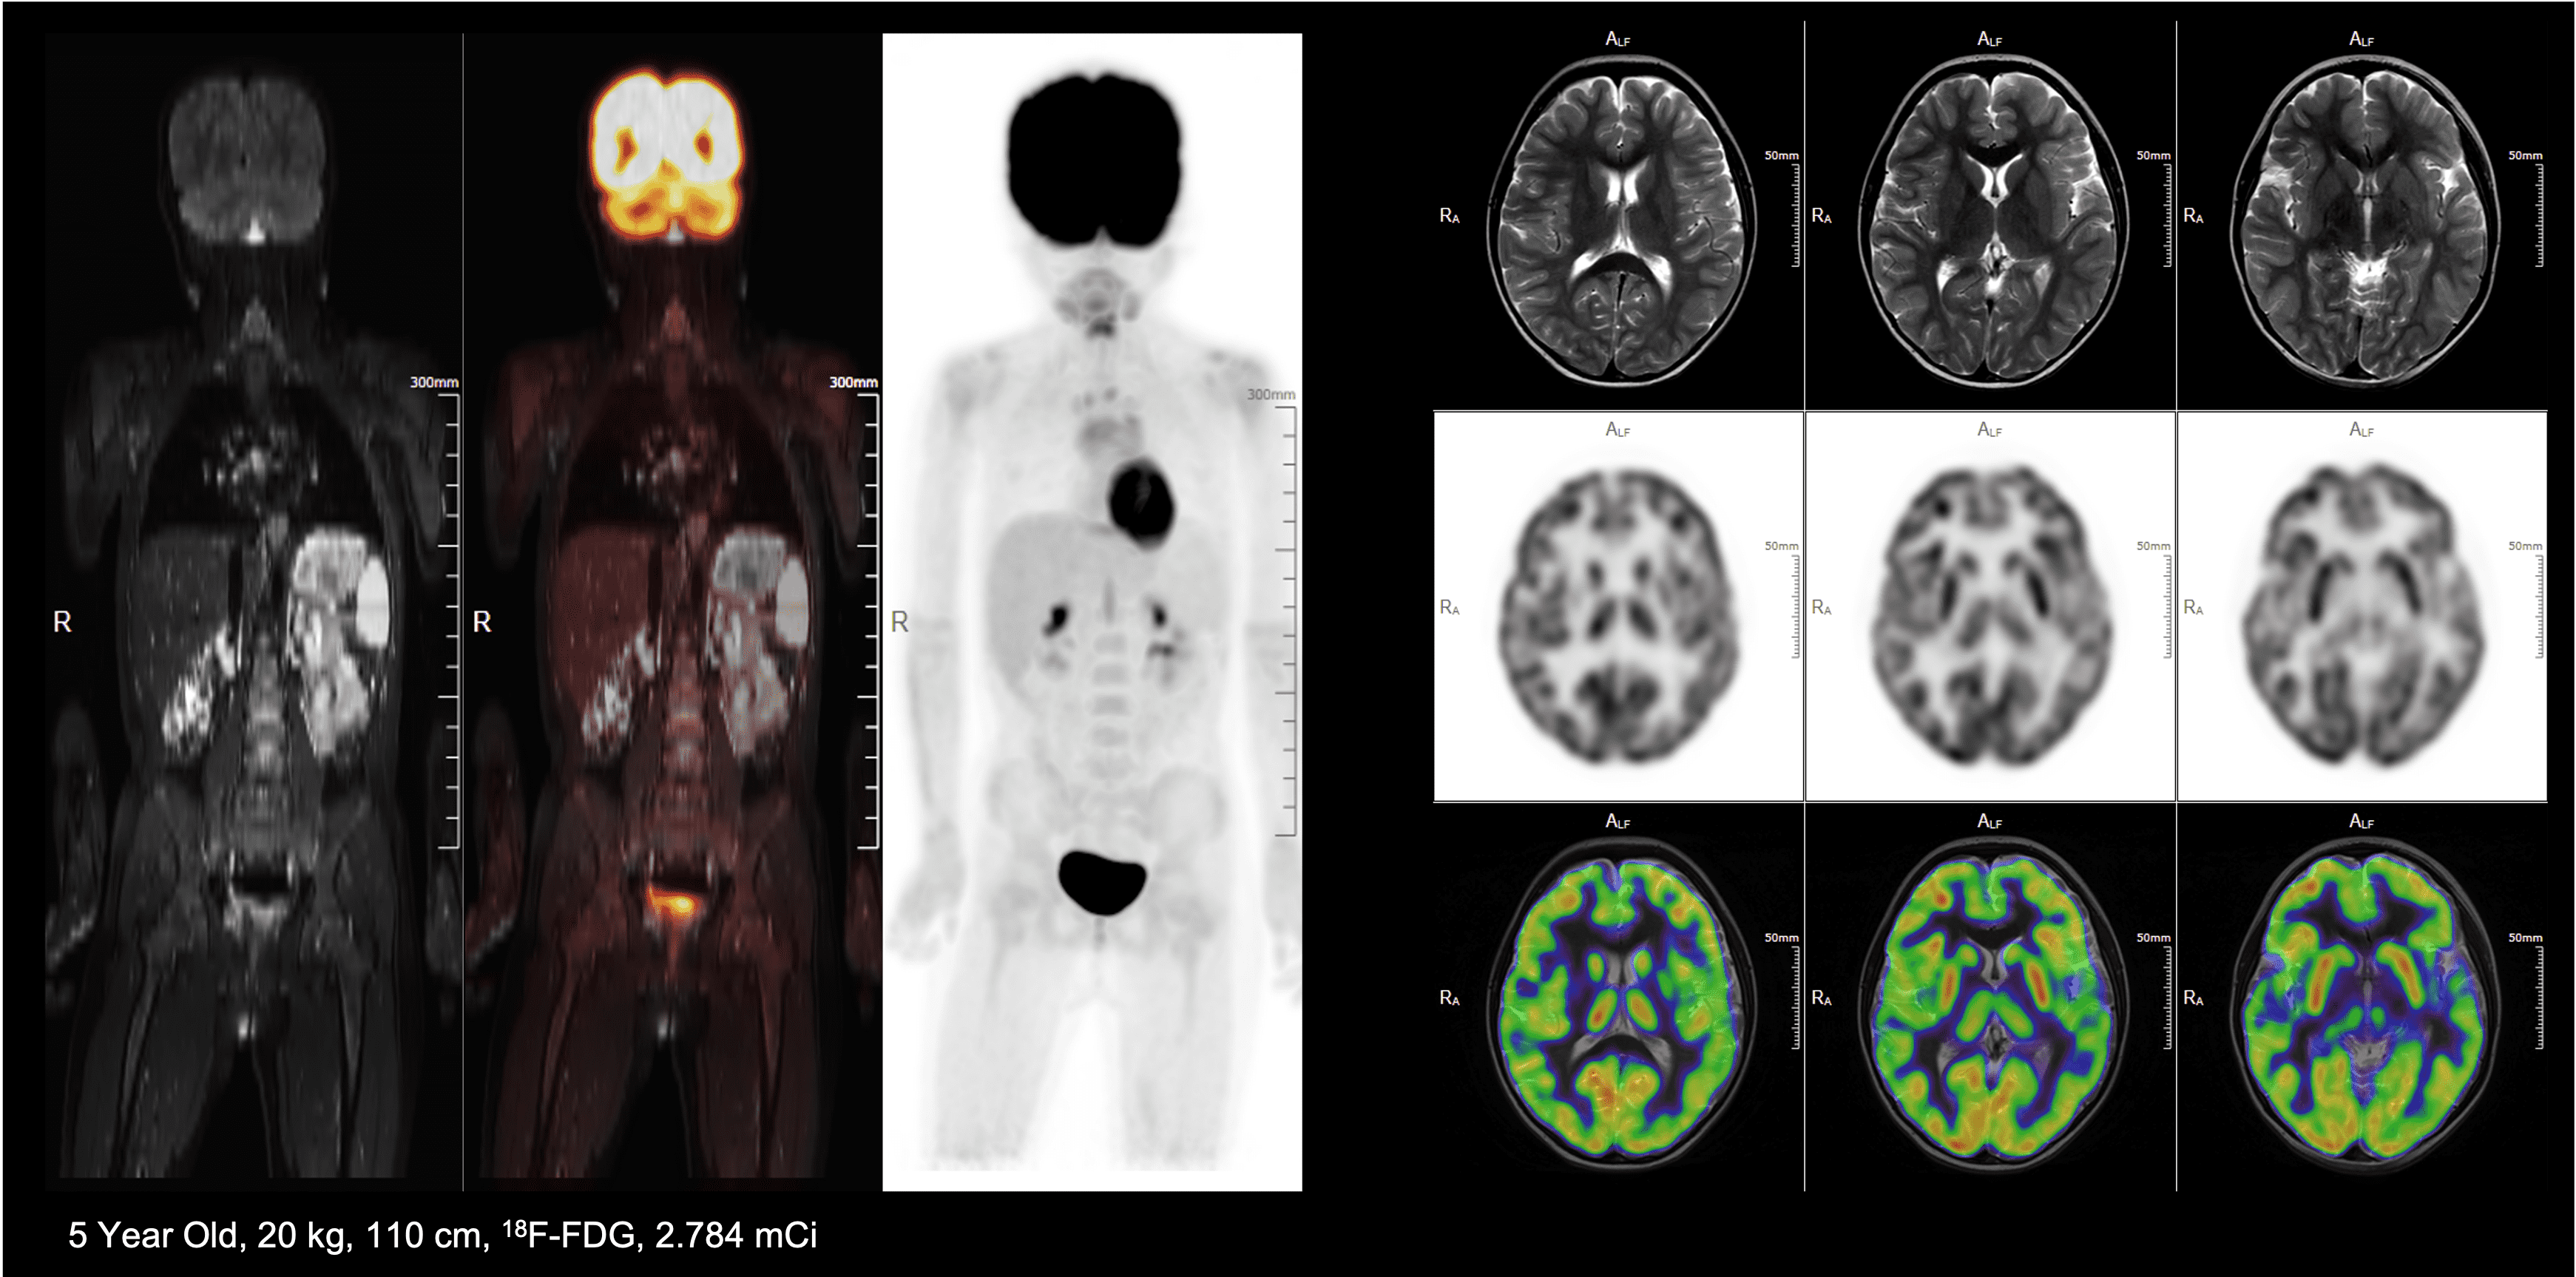

PET/MRI of a pediatric patient with lymphoma

9 min high resolution whole-body PET/MR exam with low radiation dose*

*Images Courtsey Of Nanjing First Hospital